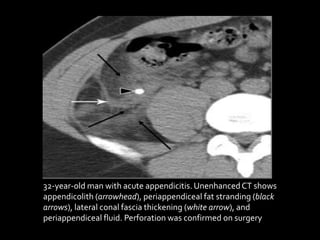

32-year-old man with acute appendicitis.UnenhancedCT shows

appendicolith (arrowhead), periappendiceal fat stranding (black

arrows), lateral conal fascia thickening (white arrow), and

periappendiceal fluid. Perforation was confirmed on surgery